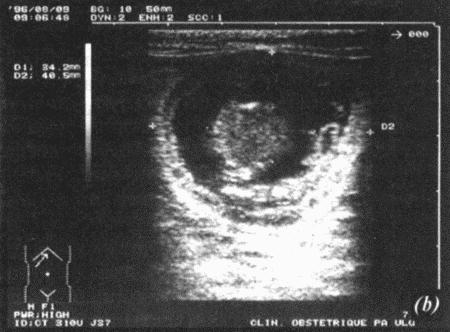

Вагинальная эндоскопия

Прекращение секреции эстрадиола фолликулами и переход их к секреции прогестерона приводят к снижению как отечности, так и васкуляризации слизистых оболочек, что сопровождается выраженным изменением характера вагинальных выделений, выявляемым с помощью вагинальной эндоскопии. На стадии проэструса слизистая оболочка становится более выпуклой и отечной, затем наблюдается ее уменьшение; по мере приближения овуляторного пика слизистая сжимается и бледнеет, в некоторых случаях становясь практически белой (фиг. 1.1). Перечисленные изменения свидетельствуют о приближении стадии, характеризующейся постепенным повышением концентрации прогестерона перед овуляцией и последующим наступлением фертильного периода. Эти изменения легко узнать, имея даже небольшую практику (фиг. 1.3), кроме того, они настолько воспроизводимы, что по набору признаков их можно оценивать полуколичественно. Вагинальная эндоскопия весьма полезна в определении оптимальных сроков вязки. По окончании фертильного периода, т. е. в начале метэструса — слизистая оболочка влагалища бледнеет и истончается, складки становятся закругленными — и что, вероятно, является наиболее характерным признаком, — слизистая в переднем отделе влагалища выглядит раздраженной и при прикосновении быстро сжимается, образуя розетку.

Фиг. 1.3.

Эндоскопическое исследование слизистой влагалища. Динамика изменений на протяжении цикла: (а) проэтрус — розовая окраска и отечность; (b) начало эструса — слизистая бледнеет, отек начинает уменьшаться (обычно перед пиком ЛГ); (c) середина эструса — слизистая бледная, уменьшение отека (сморщивание) явно выражено, что соответствует середине фертильного периода; (d) начало метэструса — видны закругленные складки, при прикосновении слизистая смыкается, образуя розетку (е) (см. Приложение)